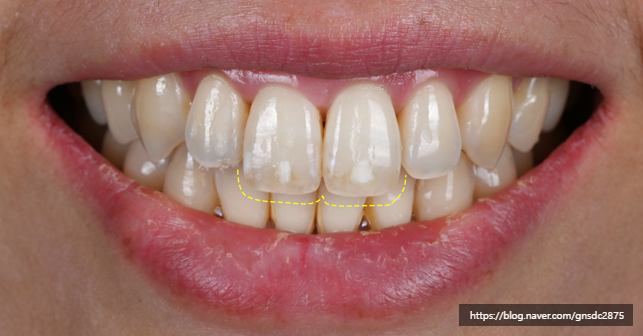

#CASE 02

백색반점이 있는 길이가 다른 앞니

다음 환자분도 양앞니의 백색반점과

미세하게 다른 치아 길이를

앞니통합치료 뉴티스로 개선하였습니다.